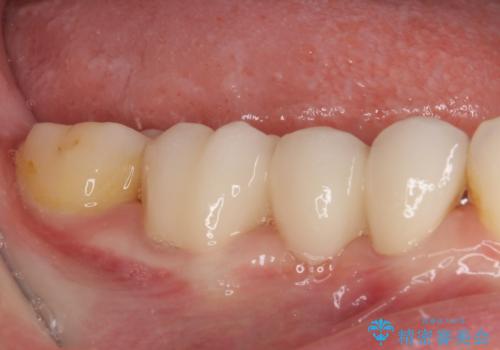

- 上下前歯のデコボコと奥歯の欠損を気にして来院された患者様です。

右下の欠損分は奥歯が倒れ込んでスペースがなくなっていたため、矯正治療により本来の位置に歯を移動させ、オールセラミックブリッジによる欠損補綴治療を行うこととしました。

全顎的にセラミッククラウンが多く装着されているため、インビザラインによる矯正治療を行うこととしました。

右下は移動量が多いため、十分な移動が達成されない場合はワイヤー装置を使用する予定としておりましたが、しっかりとマウスピースを装着してくださったため、前歯とともに十分に歯を動かすことができました。